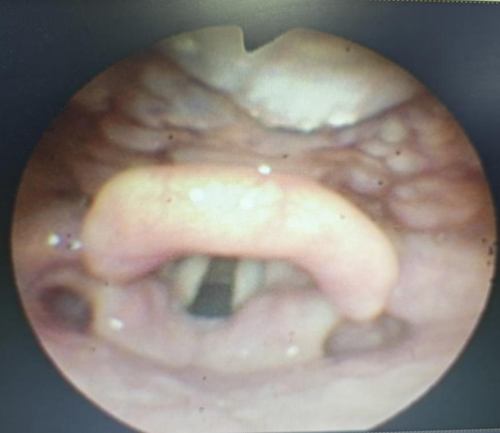

正常舌根-下咽-喉内镜检查图